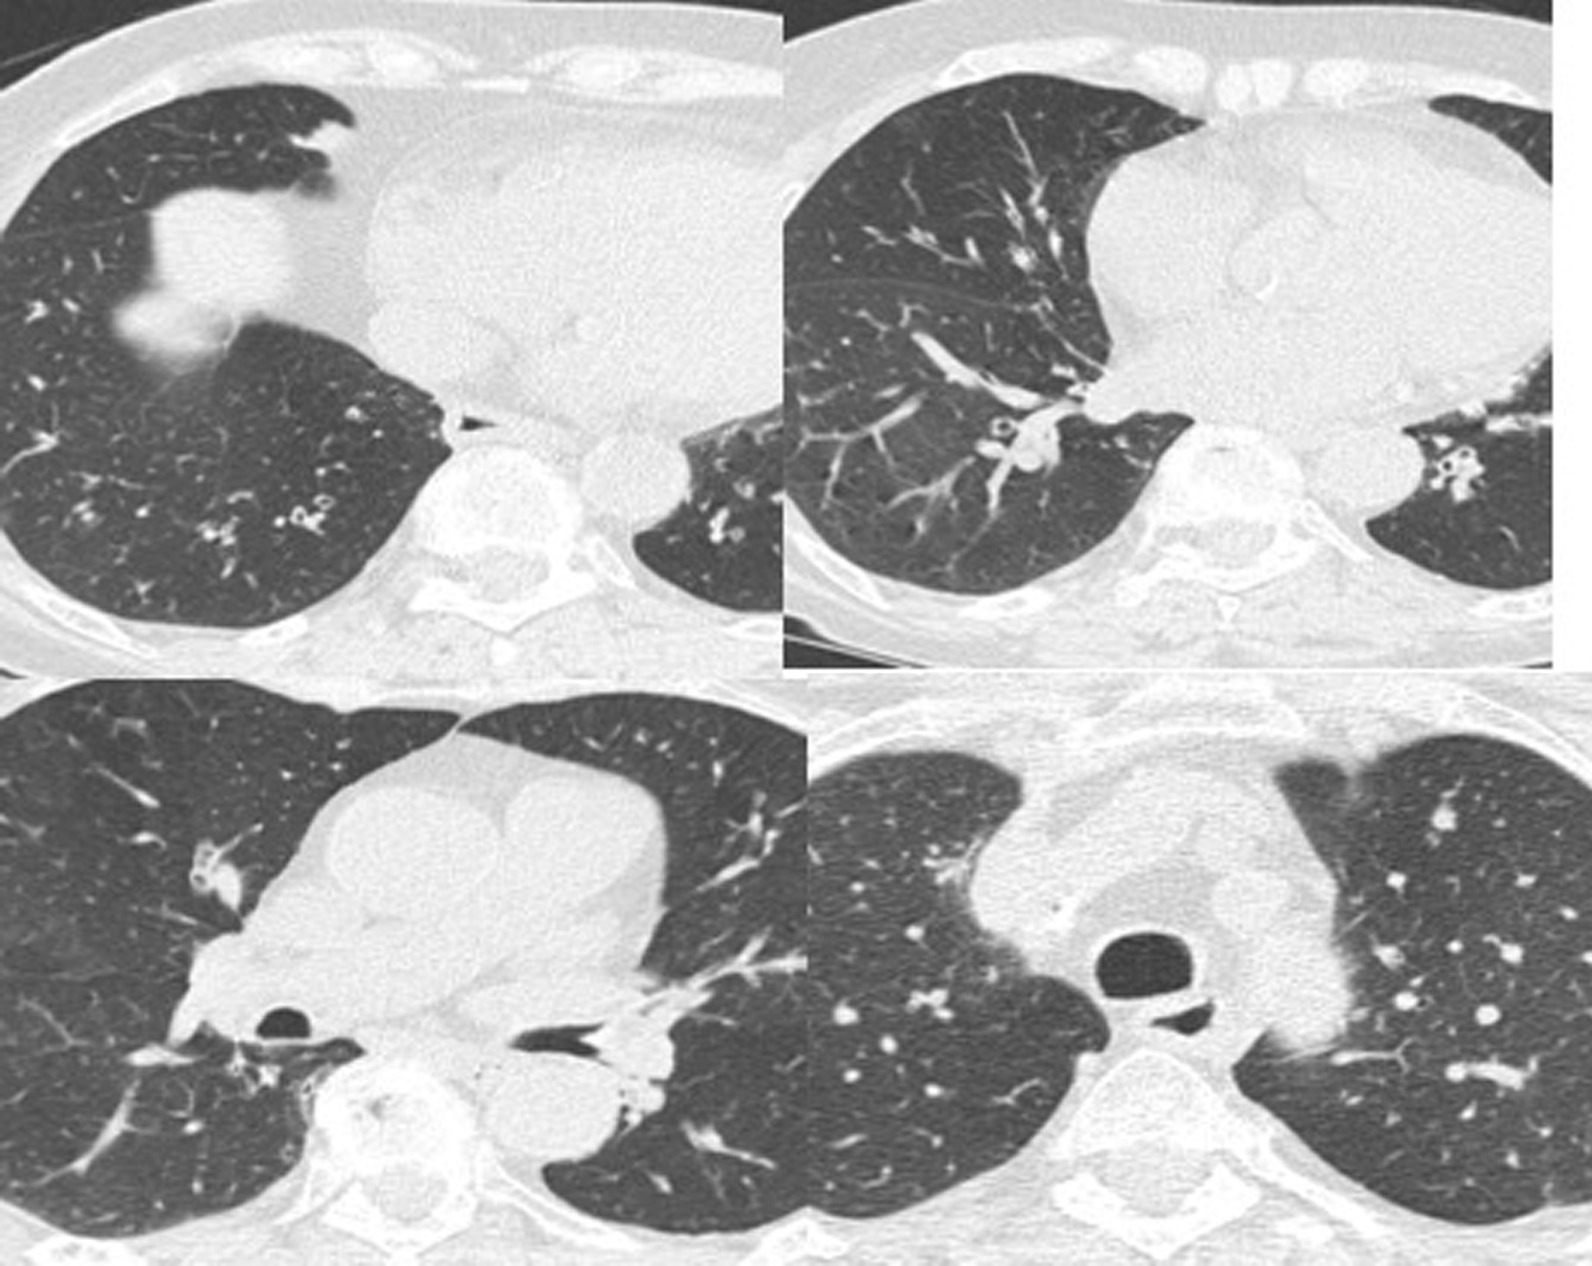

The patient complained of worsening dyspnea with wheezing. Spirometry performed at the first visit showed forced vital capacity (FVC) of 2.17 (120%), FEV1 1.64 (113%) and diffusing capacity for carbon monoxide (DLCO) of 4.11 mmol/(minute KPa), 80%. Spirometry performed at the second visit showed FVC 1.95 (100%), FEV1 1.44 (100%), Tiffeneau index of 75% and DLCO 4.11 mmol/(minute KPa), 80%. The six-minute walk test was normal. She was subjected to a methacholine challenge test, which was positive for severe hyperreactivity. Allergic skin tests for inhalants and foods were negative. A paper radioimmunosorbent test (PRIST) showed a level of 39 U/mL. The blood tests were normal except for serum alpha-1 antitrypsin (AAT) of 67 mg/L (normal value is 0.90–2.00 g/L). Chest computed tomography scan revealed the presence of small areas of air trapping and diffuse bronchiectasis (Fig. 1). Sputum cultures performed to exclude colonization of potentially pathogenic microorganisms that could be the cause of exacerbations were negative.

Fig. 1.

Chest computed tomography scan showed the presence of small areas of air trapping and diffuse bronchiectasis